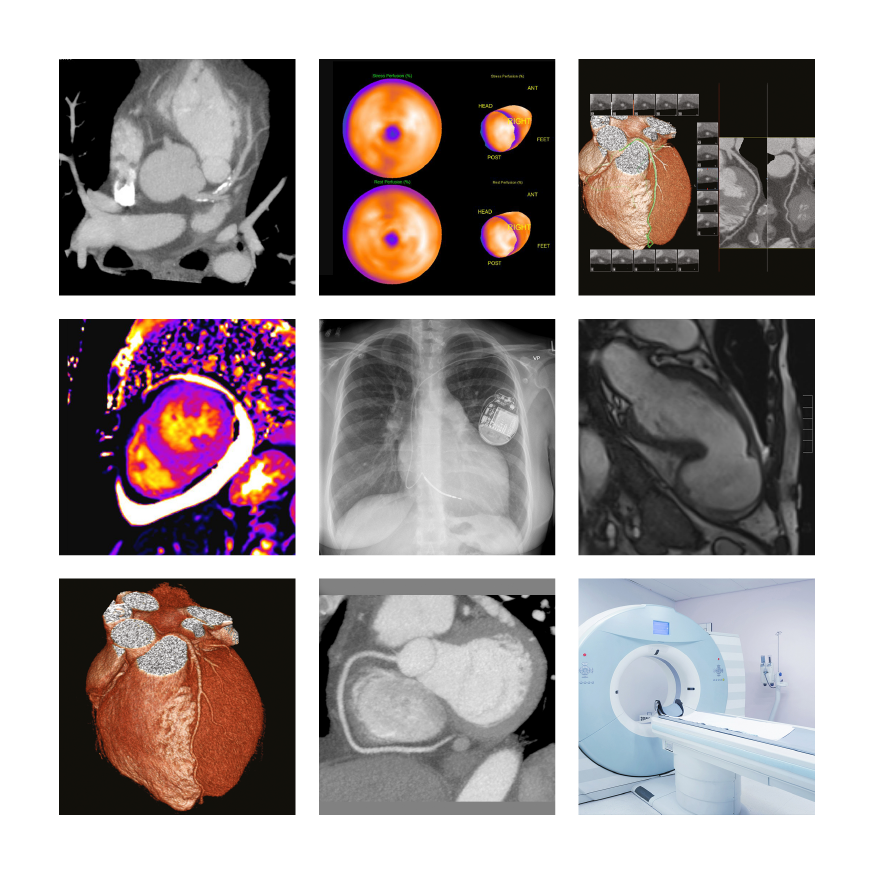

Welcome to Cardiovascular Imaging eLearning, a platform providing a comprehensive yet simple understanding of the use of different techniques for imaging the heart and vascular system in patients with different clinical presentations.

The last twenty years have seen a rapid development of cardiovascular imaging with advances in CT (Computed Tomography), MRI (Magnetic Resonance Imaging), and PET-CT with continued development in echocardiography and invasive angiography. This platform describes the different clinical cardiac presentations and the best use of the different imaging techniques for these presentations discussing their strengths and limitations based on the current evidence base.